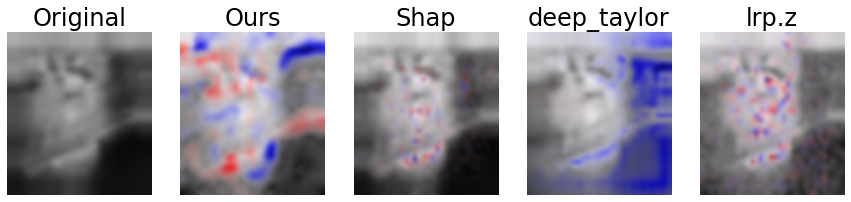

The results of the user study are listed in Tables 3 through 6 and visualized exemplarily for the LIDC-IDRI data set in Fig. 11. A qualitative comparison of our approach to DeepSHAP, DeepTaylor and LRP is depicted in Fig. 8.

BreastMNIST

On the BreastMNIST datasets our method reached average raw values of 1.45, 1.33 and 1.72 for intuitive validity, semantic meaningfulness and image quality, respectively, reaching the highest values amongst the tested algorithms, second highest was DeepTaylor with 0.91/0.90/0.75. While the results were significantly superior to DeepSHAP and LRP (, all ), the difference to DeepTaylor was not significant (), with the same pattern showing for the z-adjusted values. The average rank amongst the methods was 1.75, 1.77 and 1.64 for our approach with DeepTaylor being second with 1.99, 1.99 and 2.27, respectively. Again, results were significantly superior to DeepSHAP and LRP (, all ) and not significant for DeepTaylor (). The inter-observer reliability was between .386 and .455, implying a fair to moderate correlation. The Kaiser-Mayer-Olkin criterion was and the largest principal component was responsible for 86.5 % of the variance.